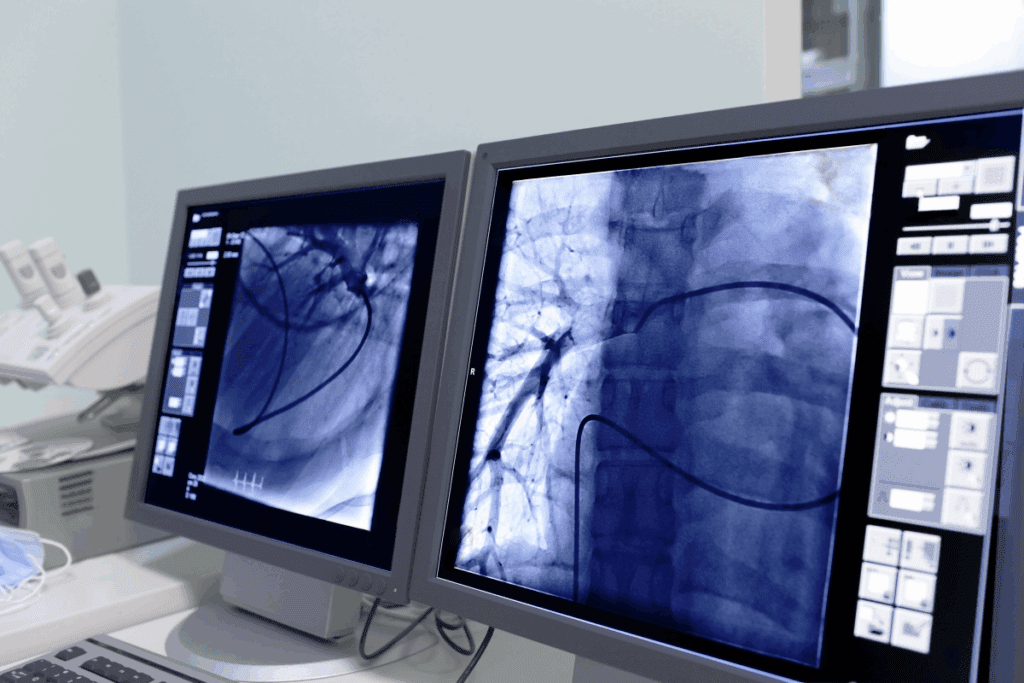

Another big difference is the use of image guidance. Tools like fluoroscopy and MRI help doctors see what they’re doing in real-time. This precision is hard to match with traditional surgery.

Angiography lets us see inside blood vessels. We use a contrast agent to spot problems like blockages. This tool is vital for planning treatments.